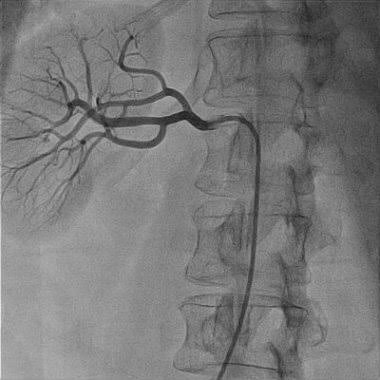

آنژیوگرافی با اشعه X نوعی از تصویربرداری است که مبتنی بر ید برای افزایش کنتراست به بدن تزریق و از رگها با استفاده از اشعه X تصویربرداری انجام میشود .

این روش بدین صورت است که تضعیف رگها در مقایسه با بافت های اطرافش زیاد خواهد بود و به راحتی گرفتگی عروق آشکار میشود همچنین روشی بنام DSA وجود دارد که یک تصویر از قبل از تزریق ماده افزایش دهنده کنتراست ویکی بعد از آن گرفته شده و دوتصور از هم کم میشود و تصویر موردنظر حاصل میشود.

بعبارت دیگر با کمک دستگاه اشعه ایکس و رنگ‌های تزریق‌شده، به‌سرعت یک سری تصاویر (آنژیوگرام) از رگ‌ها گرفته‌شده و سپس بر روی مانیتور ظاهر می‌شوند.

این تصاویر به‌طور واضحی هرگونه تنگ‌شدگی و یا انسداد عروقی را به تصویر می‌کشند و از طریق آن‌ها پزشک متوجه می‌شود که کدام‌یک از رگ‌های بدن باعث بروز مشکلات قلبی شده است.